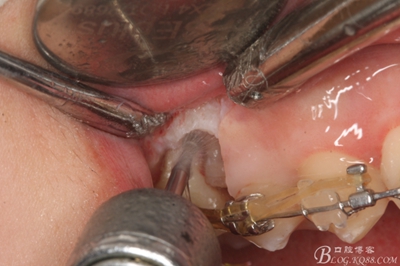

圖13. 用小球鉆去除約1mm牙槽骨,暴露15牙根面約5mm。

圖14.用小球鉆縱分15牙根